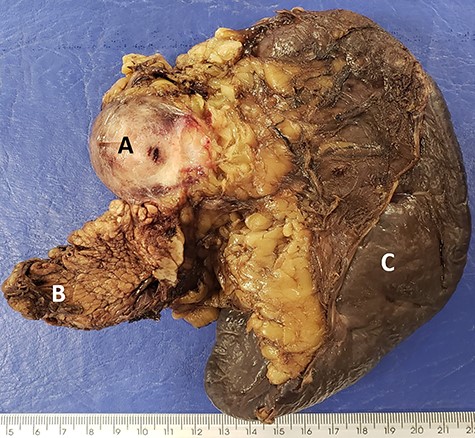

The macroscopic anatomopathological study showed a 4.3 cm diameter nodular lesion, consisting of a firm and brownish tissue, ill-defined fibrous mass in the pancreas that was diffusely infiltrative on gross and microscopic examination (Fig. 9). Histologic examination and IHC were consistent with DT. There was no involvement of the surgical margins, spleen or mesenteric LNs.

Macroscopic image showing firm and brown (A) nodular area, on the periphery of the (B) caudal region of the pancreas and (C) spleen.